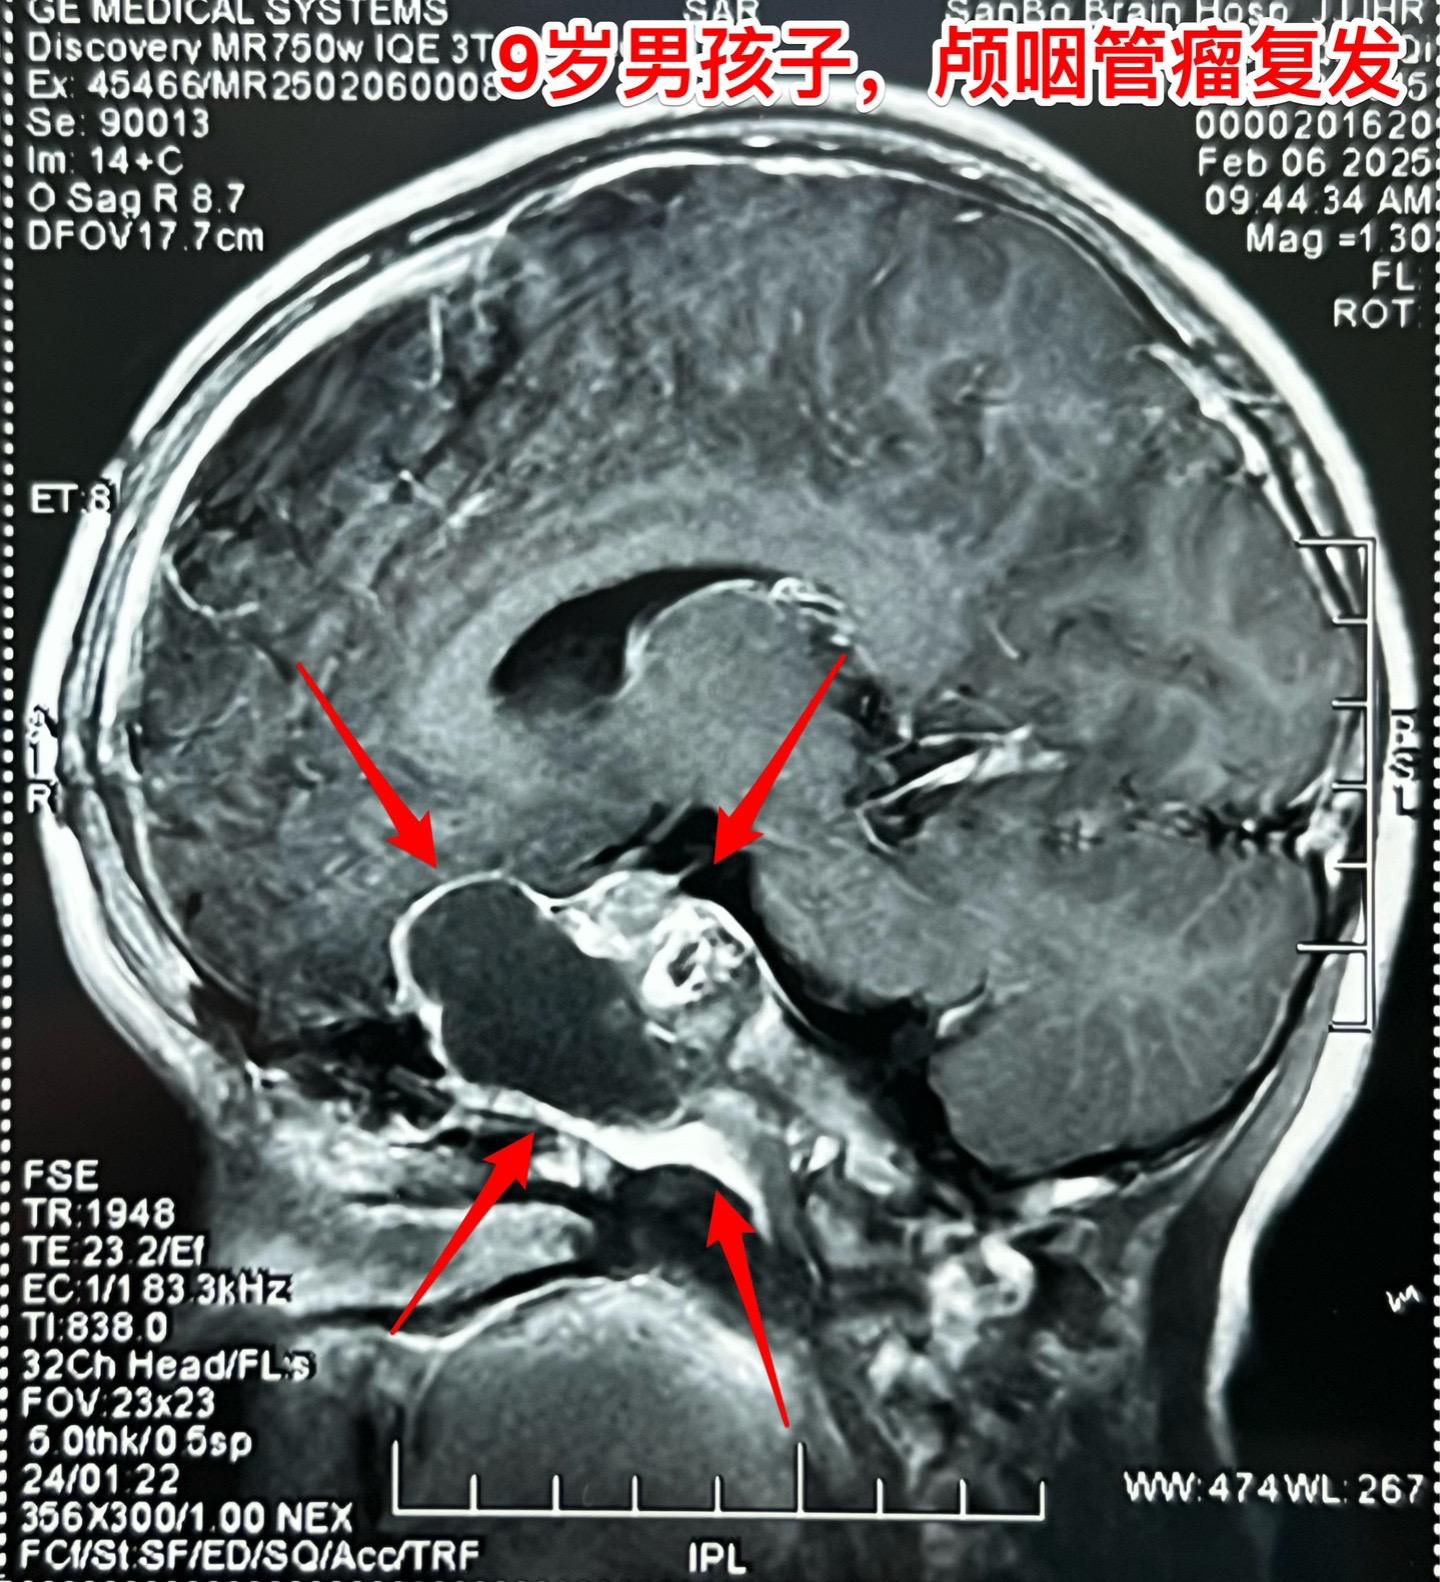

九岁男孩子颅咽管瘤复发,肿瘤生长快。南阳市男孩子2年半前曾经作了一次手...